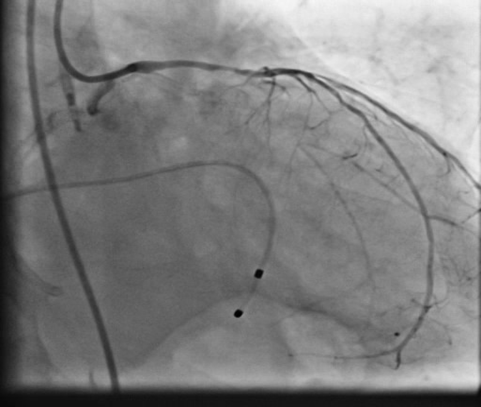

patient underwent coronary angiogram which revealed calcified triple vessel disease with near total occlusion of proximal RCA and 80% calcified stenosis in mid LAD with diseased small circumflex artery. In view of very high surgical risk he was turned down by surgical team and was advised for a high risk PCI of infarct related artery on hemodynamic support in form of IABP which was only mechanical circulatory support available apart from VA-ECMO.

PCIof right coronary artery was initiated on IABP support with amplatz left1 guided catheter and vessel was crossed with great difficulty in repeatedattempts by fielder XT followed by GAIA 2 wire over corsair microcatheter. Microcathetercould not be crossed beyond mid segment calcified CTO, so balloon dilation with0.75 mm balloon was done after which again microcatheter could not be trackedbeyond mid part. Butwe were able to exchange wire to allstar followed by rotawire byplacing microcatheter in mid segment after balloon dilation by 0.75 mm balloon. Rotablation wasdone with 1.25 mm burr at 1,60,00 rpm repeatedly from proximal to mid distalpart. Lesionstill looked unprepared as repeated postdilation with2.25*15 mm followed by 2.5*15 mm non compliant balloon at high pressures showedunexpanded balloon. Againlesion preparation was done with 2.5*15 mm wolverine cutting balloon repeatedlyat high pressures which led to adequate luminal gain and calcium cracks as seenon IVUS run. AfterIVUS run again high pressure balloon dilation was done with wolverine 2.5*15 mmballoon followed by 2.5*12 mm non compliant balloon at 28 atm toadequately prepare the lesion before stent deployment. Stentingwas done with 2.5*32 mm DES, 2.75*32 mm DES, and 3*24 mm DES from distal toproximal in overlapping fashion. Thenfinally high pressure post dilation was done with 2.75*15 mm followed by 3*15mm non compliant balloon and adequate stent expansion was achieved with TIMI 3 flow.